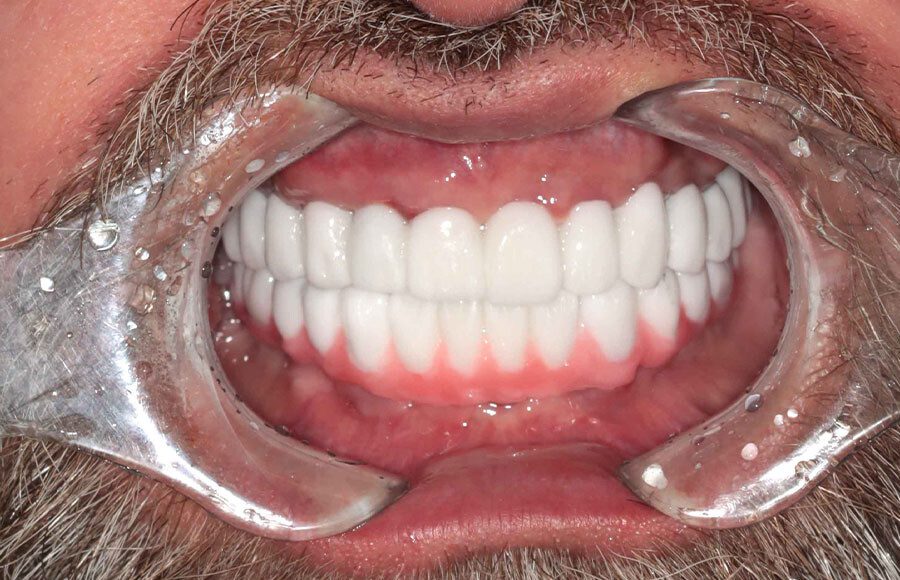

Final prostheses, intraoral, frontal. Homecare is still a problem. The final restorations are much kinder to the tissues and we hope this will resolve some of the inflammation.

Post-treatment panoramic image. This treatment is as good as humans can do in 2025. This patient was undecided whether to keep his teeth. We gave him the chance to consider this option but later he decided to have full mouth implants. We changed gears and were able to deliver World Class outcomes. We continue to encourage better homecare. This patient is from out of state so we haven’t seen his tissues in almost a year.